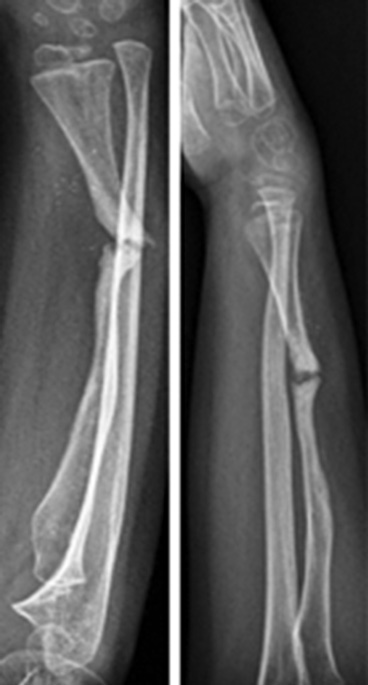

В июне 2015 г. были отмечены признаки местной резорбции кости в области переломов, и в связи с подозрением на синдром Горхема – Стоута проведены магнитно-резонансная томография и консультация со специалистом по редким заболеваниям (рис. 3).

Рис. 3. В области переломов — признаки локальной резорбции кости

Была выполнена биопсия кости, и по заключению двух разных итальянских центров синдром Горхема – Стоута был исключен, так как выявлены реактивная костная ткань с аномальной васкуляризацией, некротические костно-хрящевые фрагменты и гигантские мононуклеарные клетки. Несмотря на то что пациент поступил в нашу больницу с этими результатами, было решено повторить биопсию, и исключение синдрома Горхема – Стоута было подтверждено. После этого провели дополнительные лабораторные исследования и консультации с большим количеством специалистов, чтобы исключить все причины, которые могли привести к обширному остеолизу. Спустя 11 мес. после последней травмы произведена новая операция на месте перелома с иссечением ткани и имплантированием аутологичного трансплантата малоберцовой кости с факторами роста костного мозга. Трансплантат стабилизирован спицами Киршнера (рис. 4).

Рис. 4. Рентгенограмма до и после иссечения ткани, аутологичная малоберцовая кость с костномозговыми факторами роста, аутотрансплантат стабилизирован интрамедуллярной спицей Киршнера